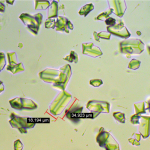

1.Analiz Hizmeti: Klinik biyokimya, endokrinoloji, hematoloji (Hemogram) ve seroloji (ICT ve IFA) alanlarında kapsamlı hizmet verilmektedir.

3.Araştırma: Araştırma projeleri ile laboratuvar tanıdaki hedeflerimiz; ülkemizdeki hayvan sağlığının korunmasına katkı sağlamak ve veteriner hekim adaylarımızın bilgi ve becerilerinin gelişmesini sağlamaktır. Fakültemiz aktif olarak mesleki eğitimde klinik uygulamanın önemli bir bileşeni olan laboratuvar tanı ile bilimsel araştırma çalışmalarını yürütmektedir.